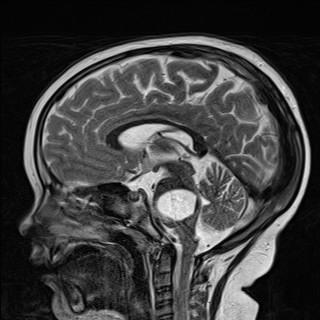

• MRI results from yesterday

We have had some fantastic news from Caidens MRI scan yesterday. His tumour is responding to the radiotherapy treatment. We have had some shrinkage since his last scan 6 weeks ago!! This is such a relief to know that our decision to put him through another round of radiation, after finding out his tumour had doubled in size was the right decision to make. It's so scary as a parent having to make such huge life threatening decisions, in hope that it gives our son more quality time here with us.

It's been 2 weeks today since Caidens radiation treatment ended... and we have no growth!! We can clearly see the radiation is doing its job killing off the cancer cells of the tumour in todays images, as the tumour diffusion is not as dense now as it was back in January.

Between his MRI in December and his last MRI in January the tumour almost doubled in size :( ... but today after completing radiation it has not grown since the last scan! :)

Sadly Caidens recent MRI on the 4th of January confirmed that his brain stem tumour is progressing. The tumour had grown alot in just 4 short weeks. We had been told by our oncologist that his MRI on the 7th of December looked concerning in areas, but because Caiden was still doing amazing we had hoped that they were wrong. But 3 weeks after that MRI we noticed Caidens symptoms started to increase. We are devastated.

Caiden had an MRI on Wednesday. He has been doing so amazing the last few months. Unfortunately the results of the MRI were not what we had hoped for. Based on how great he is doing we had expected to see a stable tumour or some shrinkage. Sadly all the medical team are concerned about some changes to his brain stem tumour. There is a new diffuse area that is starting to take over the cystic component of his tumour which is a cause for concern. When tumour progression begins that normally means a very rapid decline. Oncologist advises it's best to start another round of radiation before symptoms start to appear, but we are very hesitant. He's doing so well right now, & we don't want the quality of life that he has now to deteriorate with the radiation side effects.

Caiden had his most recent MRI last week. They have labeled this MRI as inconclusive due to not wanting to label anything, and because they are not certain about what they can see on the scan. Caidens tumour has always looked different to other DIPG tumours, and because of his not being a typical looking tumour no one knows how his will react.

He will have another MRI scan in 7 weeks time to decide if they are seeing tumour progression, or if it is cystic fluid leaking into the cerebellum of the brain, or if it is radiation necrosis. We pray with all we have that it's not tumour progression.